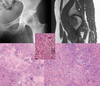

What is the structure

outlined by the black arrow in Figure 85b?

Birbeck granules (diagnostic of LCH)

LCH is also confirmed by CD1a

immunohistochemical staining.